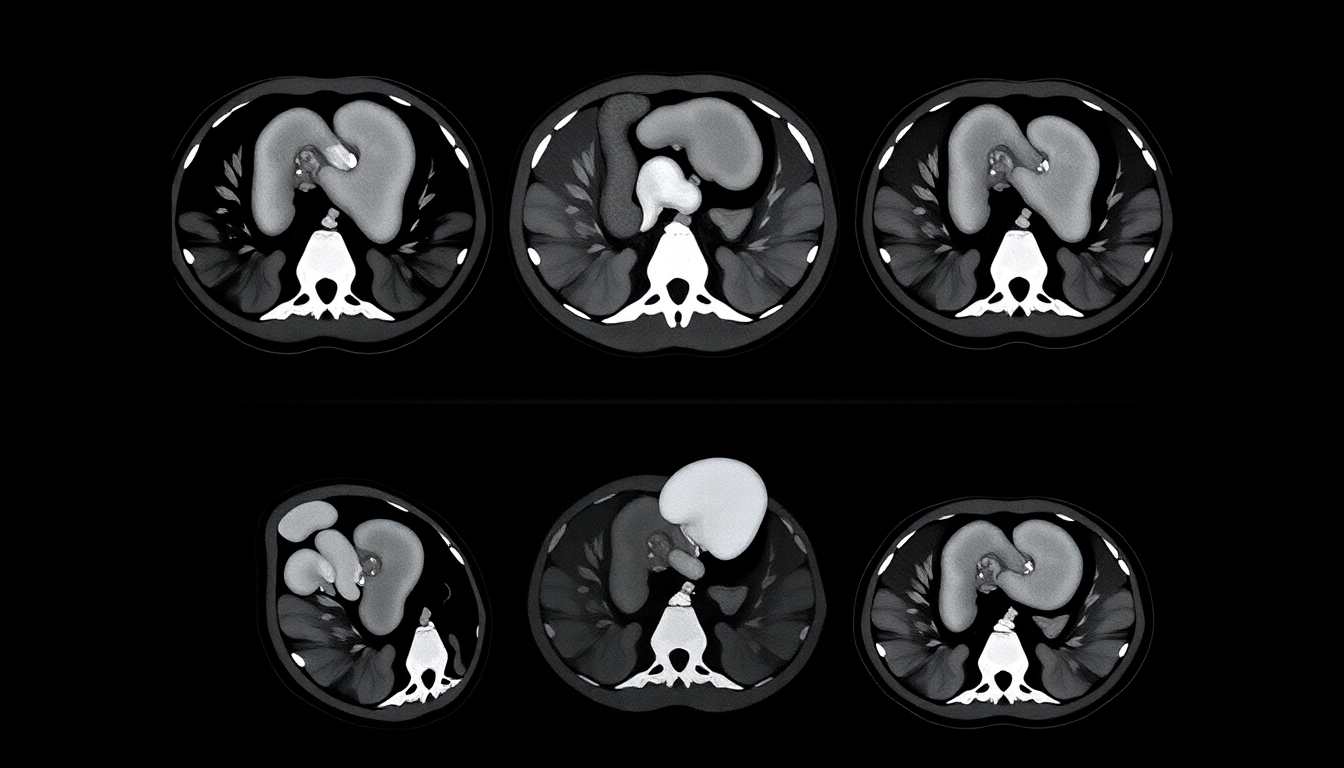

Acute Appendicitis: Diagnosis & Treatment

Key Differential Diagnoses (1)

• Gastroenteritis: Diffuse pain with vomiting/diarrhea, no localized tenderness

• Mesenteric lymphadenitis: Common in children post-viral infection

• UTI/Renal stone: Flank pain with dysuria/hematuria

• Gynecological causes: Ectopic pregnancy, ovarian torsion in females

Key Differential Diagnoses (2)

• Crohn's disease: Chronic diarrhea + weight loss with RLQ pain

• Appendiceal abscess: Fever/chills with localized tenderness

• Meckel's diverticulitis: Mimics appendicitis in children

• Right-sided diverticulitis: More common in elderly patients